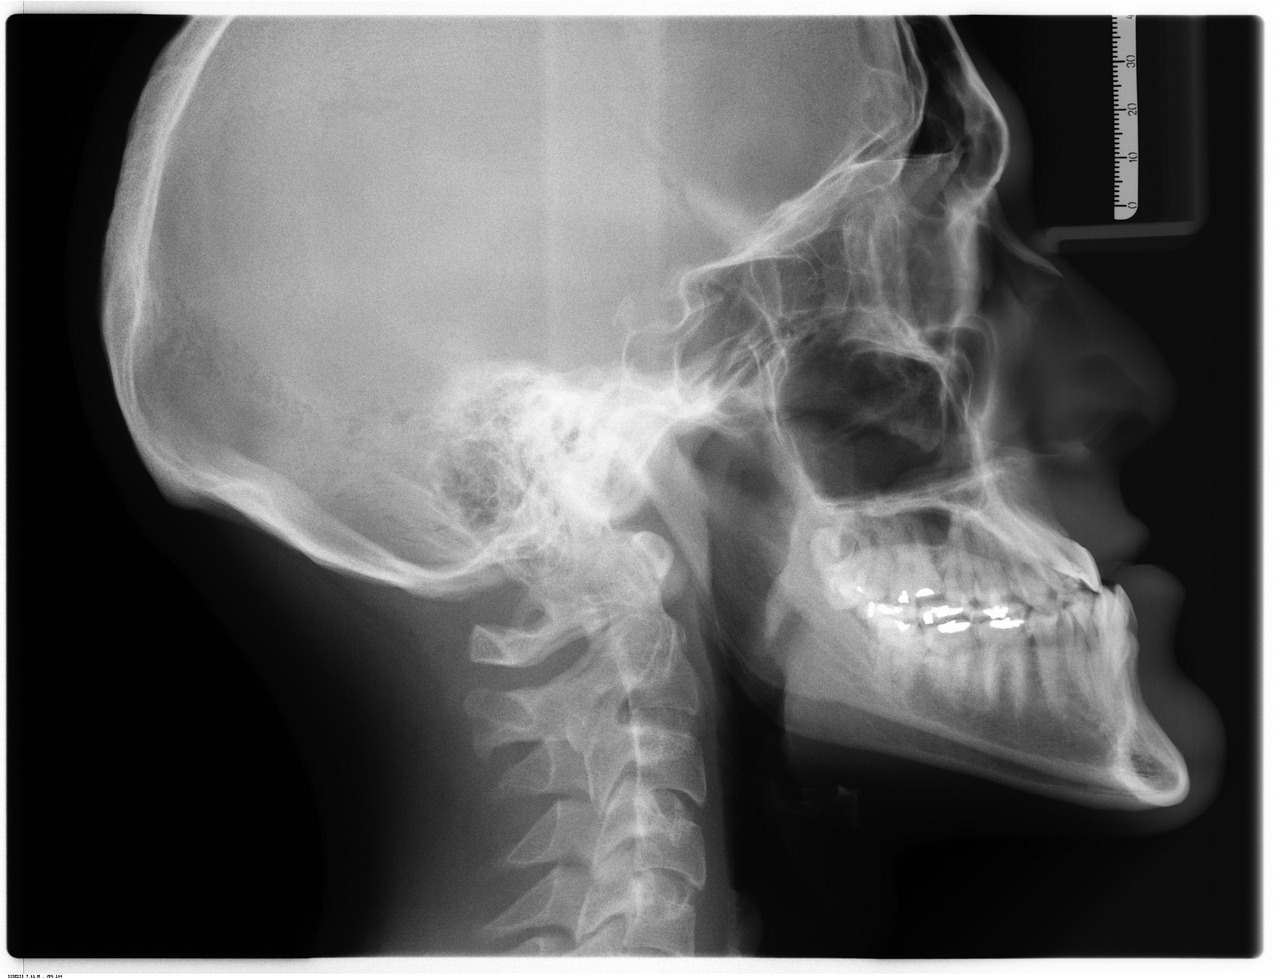

- La Imagen para el Diagnóstico incluye técnicas como la radiografía, la ecografía y la resonancia magnética.

- Radiografías: Posicionamos al paciente en la máquina y ajustamos los parámetros necesarios.